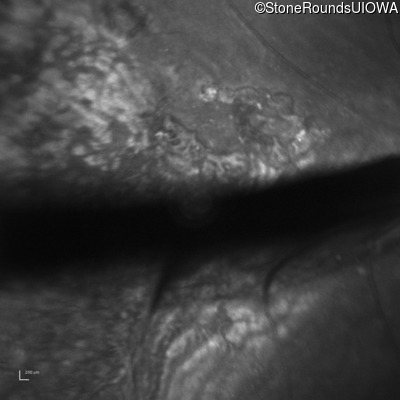

Infrared Fundus Photograph - Right - 20/200 sc

Exemplar